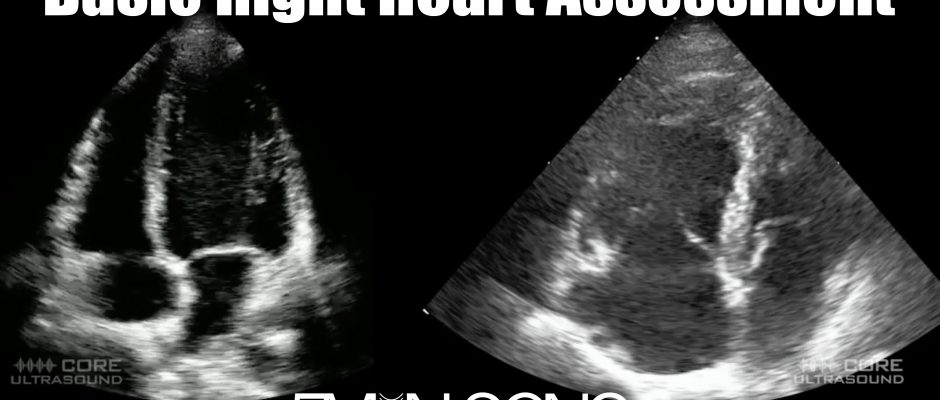

5 Min Sono – Right Heart Assessment

In this Five Minute Sono video, we go over how to use bedside ultrasound to view and evaluate the right heart. Peer reviewed by Dr. Ben Smith on 6/28/21 Click HERE to check out our Pro courses, where you can follow your progress and accuracy while earning CME.